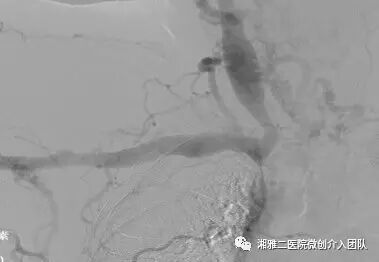

穿刺成功后行顺行性造影,了解狭窄的部位和程度

造影所见,可见无名静脉闭塞并侧枝形成